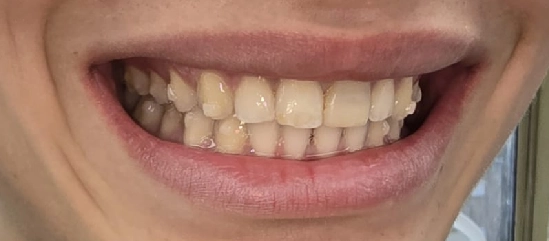

תמונות לפני ואחרי טיפול

לפני

ק.ר., בן 12, הגיע למרפאה עם מקרה אורתודונטי מורכב, שכלל שילוב של בעיה סגרית, צפיפות דנטלית ואתגר אסתטי משמעותי באזור הקדמי. בבדיקה נמצא סגר עובר אופקי מוגדל, סגר אסימטרי עם יחסי קלס 2 בצד ימין באזור הטוחנות, יחס טוחנות תקין בצד שמאל, אך יחסי קלס 2 באזור הניבים בשני הצדדים. בנוסף נצפתה צפיפות באזור החותכות העליונות, עם חפיפה בין שיניים 11 ו 21, וכן צפיפות גם בקשת התחתונה.